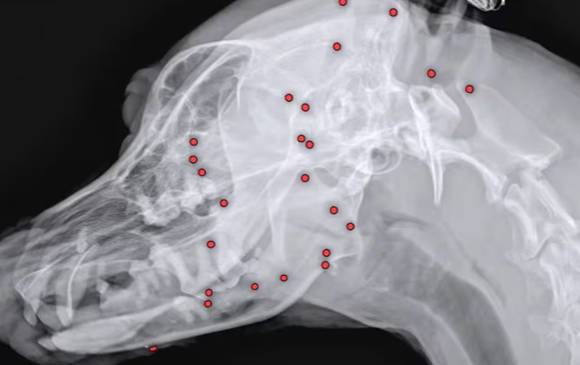

25일 'VIP동물의료센터'에 따르면 최근 구조된 유기견 백구의 몸에서 70개가 넘는 산탄총 파편이 박혀 있는 것이 확인됐다.

구조 당시 백구의 겉모습으로는 총알 자국을 확인하기 어려웠다고 한다. 해외 입양을 앞두고 건강 검진을 위해 X레이 촬영을 했다가 산탄총 파편을 발견했고, 이 때문에 백구의 입양도 불가능해졌다.

이에 동물 병원 측은 곧바로 X-ray, CT(컴퓨터 단층촬영) 등 정밀 검사를 진행 뒤 수술을 결정했다.

산탄총 파편 제거 수술은 3시간 넘게 진행됐다. 맨눈으로 탄알을 다 확인할 수 없어 투시기를 이용해 수술 시간이 길어졌다.

안승엽 VIP동물의료센터 원장은 "총알이 머리 쪽부터 어깨, 가슴통, 엉덩이, 다리까지 너무 많이 있었다"며 "살아있는 게 기적"이라고 설명했다.

이어 "탄알을 한 번에 다 제거하기는 현실적으로 어려워 백구의 얼굴을 위주로 최대한 많이 제거하는 방향을 선택했다. 총 26개의 파편을 제거했다"고도 전했다.